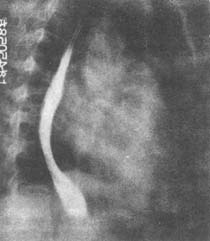

半數病兒有肉肯血尿;鏡下血尿幾乎見於所有病例。肉眼血尿時尿色可呈洗肉水樣、菸灰色、棕紅色或鮮紅色等。血尿顏色的不同和尿的酸鹼度有關;酸性尿呈菸灰或棕紅色,中性或鹼性尿呈鮮紅或洗肉水樣。肉眼血尿嚴重時可伴排尿不適甚至排尿困難。通常肉眼血尿1~2周后即轉為鏡下血尿,少數持續3~4周。也可因感染、勞累而暫時反覆。鏡下血尿持續1~3月,少數延續半年或更久,但絕大多數可恢復。血尿同時常伴程度不等的蛋白尿,一般為輕至中度,少數可達腎病水平。尿量減少並不少見,但真正發殿至少尿或無尿者為少數。